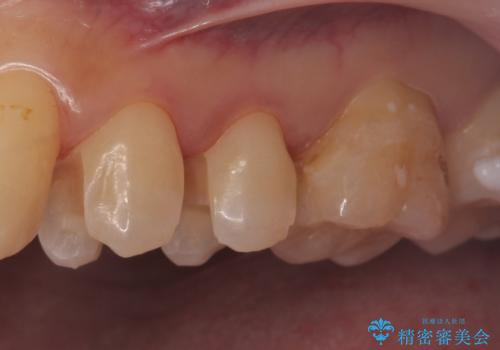

セラミックの詰め物(e-maxインレー)にて治療を行いました。

- e-maxインレー 7.7万円 ×2本費用は治療当時の料金となります

セラミックの詰め物(e-maxインレー)は、歯と詰め物の隙間がなく

虫歯の再発リスクを下げる事ができます。